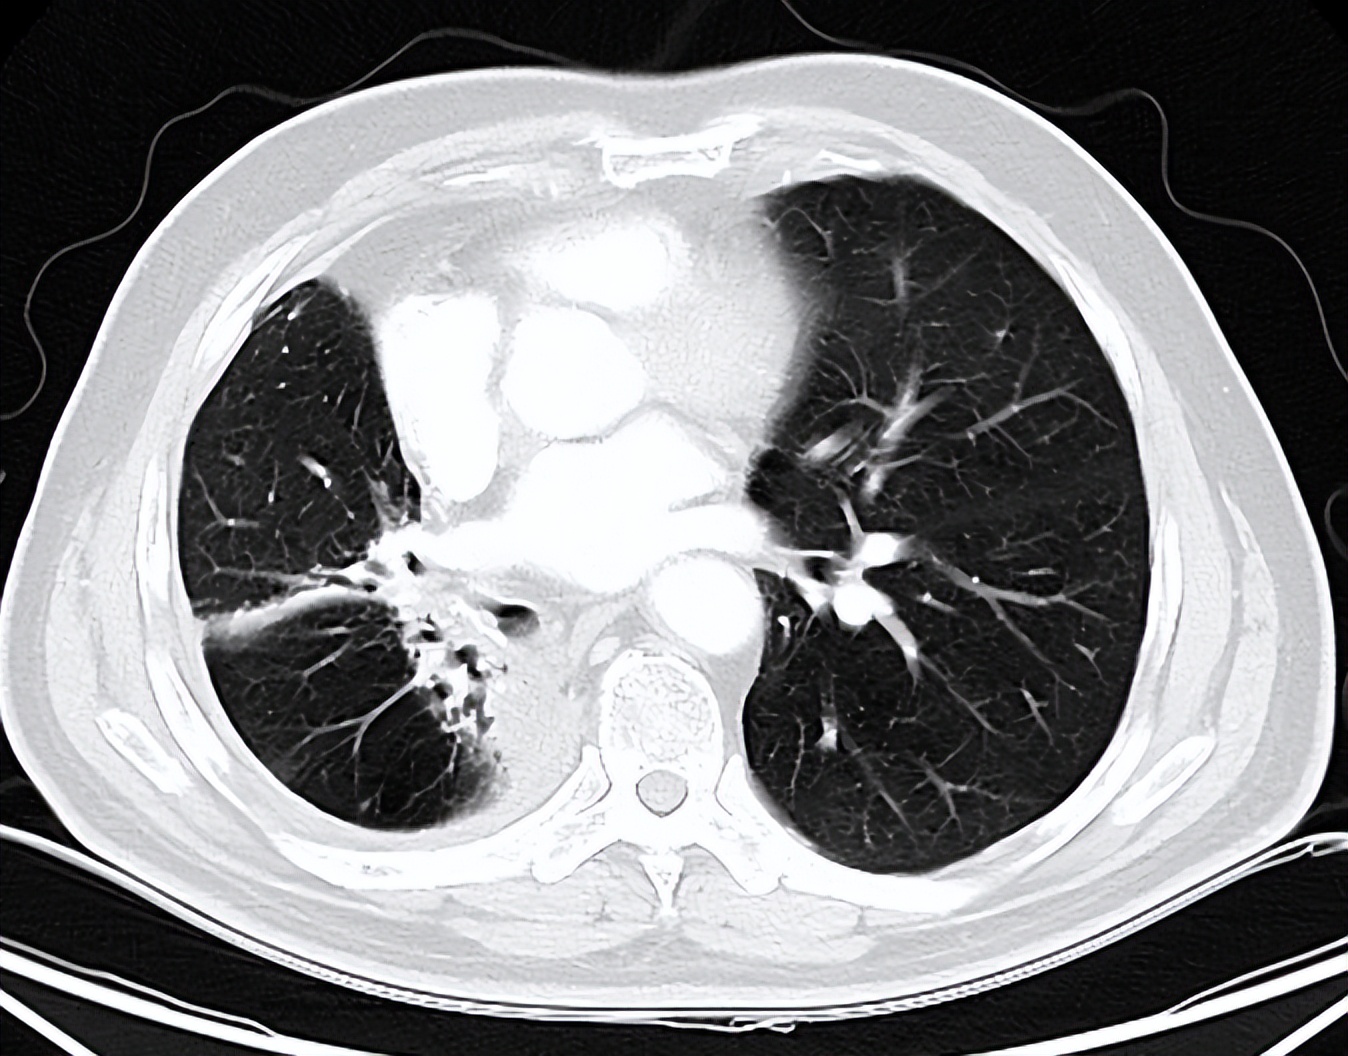

(2015年5月8日胸部CT提示右肺下叶背段空洞)

(2018年5月20日胸部CT)

(2018年10月9日胸部CT见右肺中叶放疗后改变)

(2022年5月27日胸部CT提示病灶稳定)